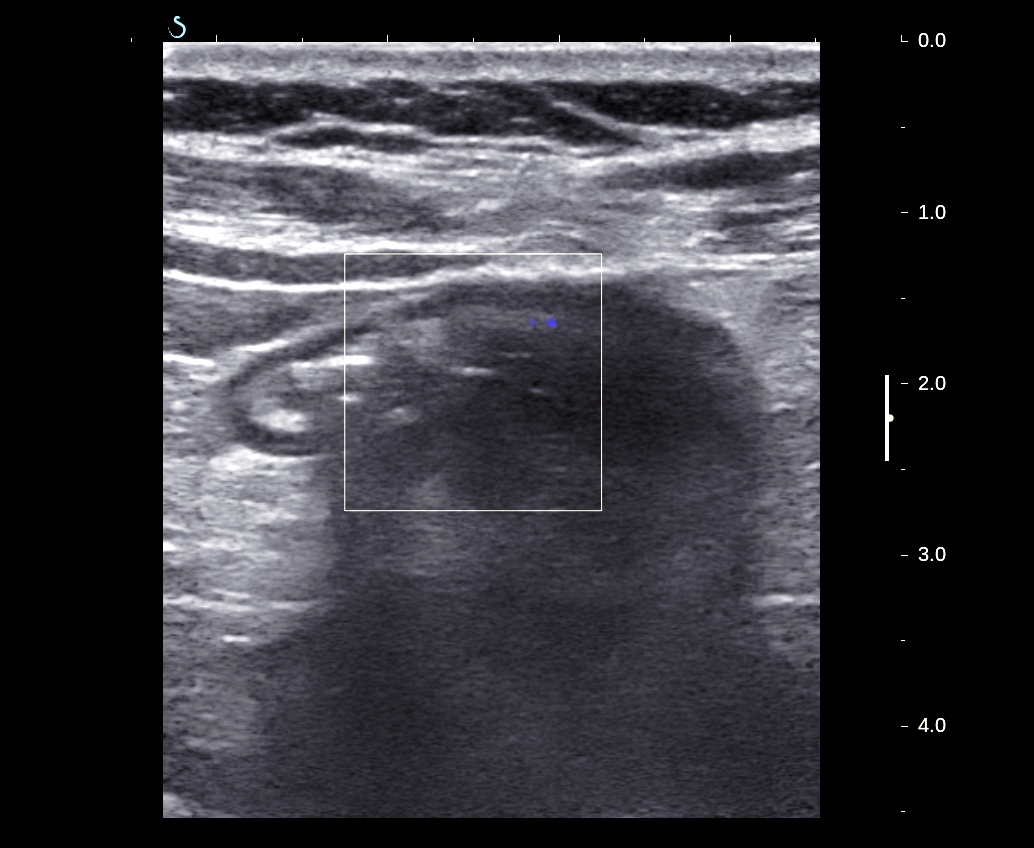

Ultrasound scan at liver:

US1.detects big mass near gallblader liked a bowel loop dilated.

US 2: right colon dilated with multiple layers which is oignon sign.

US3. Coecum moved up near liver connected with one cystic mass.

US 4 cystic mass is liquid with multiple rings [oignon sign] typical of mucineous cyst of appendix.